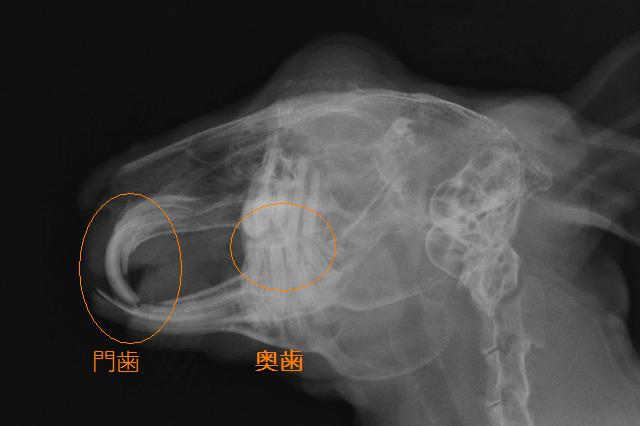

写真は門歯の噛み合わせが悪くなったウサギの横から見たレントゲン写真です。

門歯のすり減り方の異常と、奥歯が伸びすぎている様子です。 Img5933-2.jpg